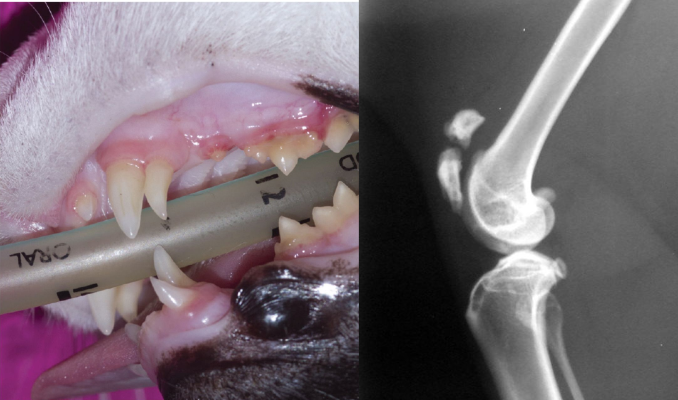

물론 꼭 유치뿐 아니라 하악이나 상항 등 얼굴쪽 뼈 및 골막 증식, 치아저하증, 치근 흡수, 치근 기형 및 맹출되지 않은 영구 치아등이 있는 경우에도 무릎골이 골절될 수 있다는것.

만약 치아에 현재 이상이 있으면서 다리를 절뚝 거리는 고양이가 있다면 이 관계성에 대해서 고려해야 한다.